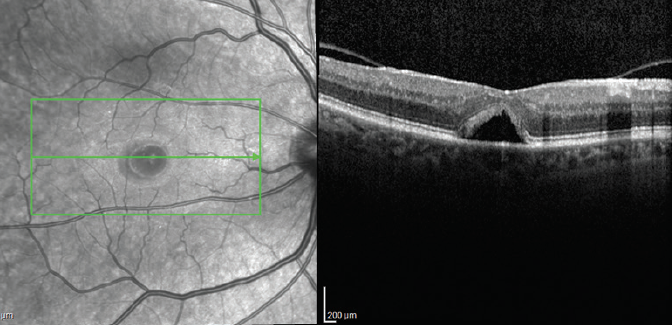

His fundus exam revealed macular edema OD; it was normal OS. Spectralis OCT (Heidelberg Engineering) high-speed 25-raster macular scans through, above, and below the fovea OD revealed macular edema and subretinal fluid (Figure 1). As the appearance was suggestive of a macular hole (MH), a high-density OCT scan was performed, revealing a small MH missed during the standard OCT scan (Figure 2).

Figure 2. High-density OCT scan through the fovea demonstrating a small MH.